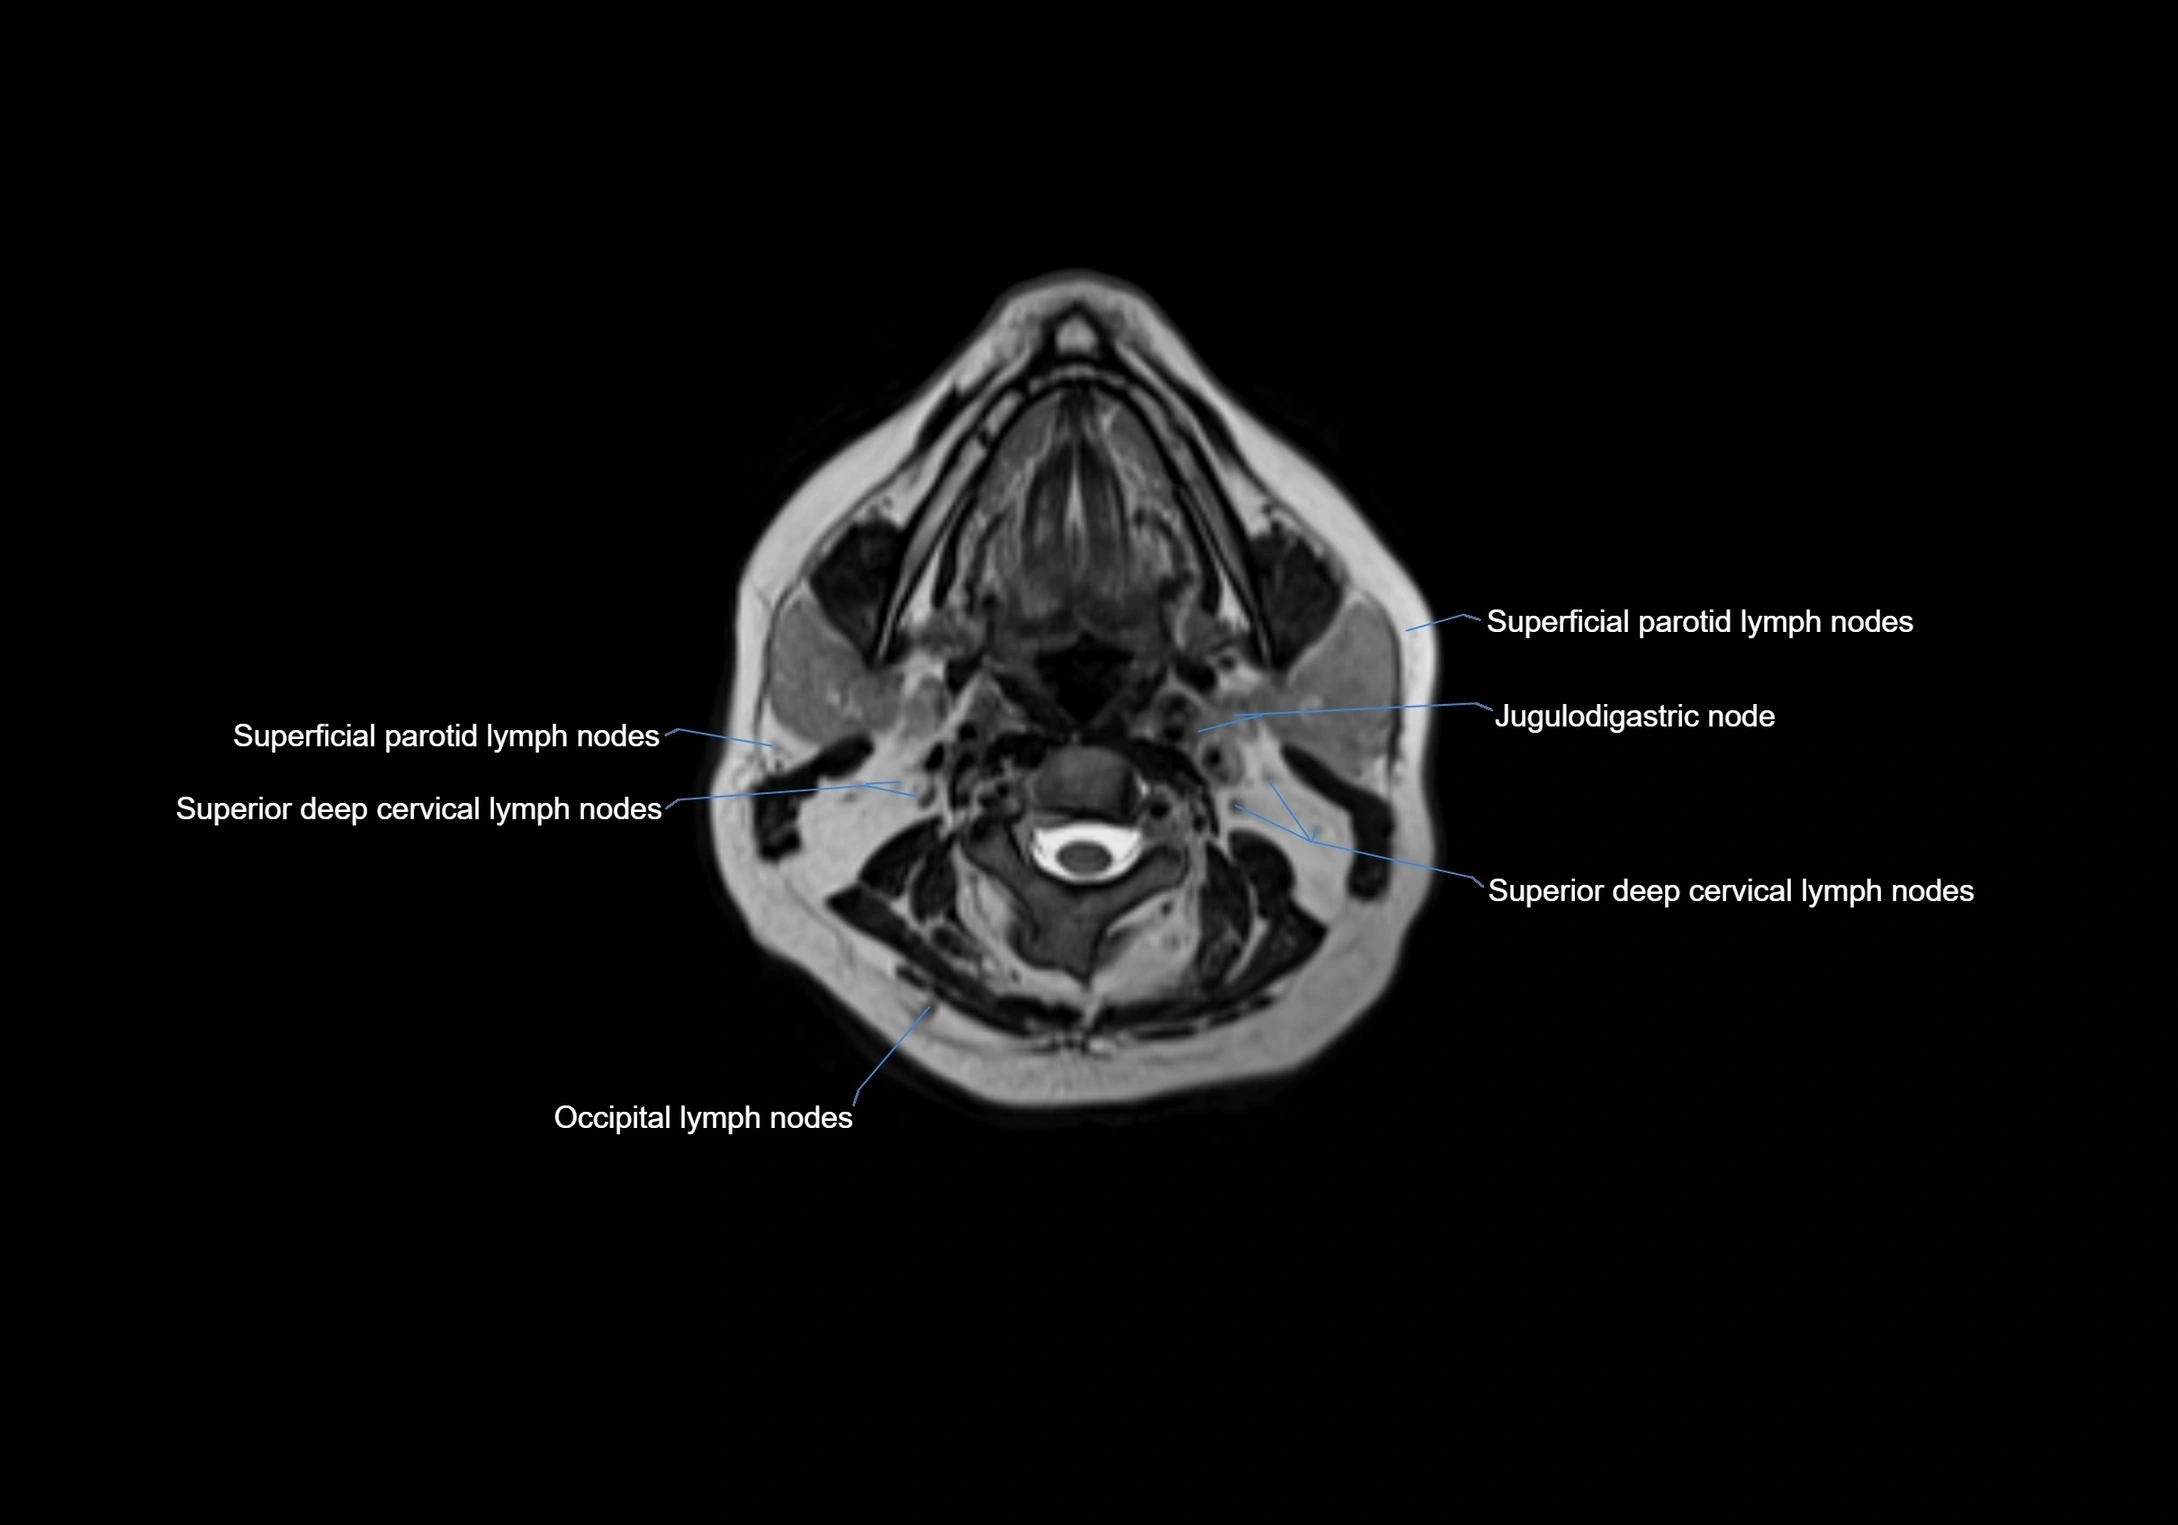

MRI Appearance

T1-weighted images:

• Normal accessory nodes appear as small, oval hypointense to intermediate signal structures within subcutaneous fat

• Surrounded by hyperintense fat, enhancing contrast for visualization

• Pathological nodes may appear enlarged or rounded, sometimes with cortical thickening

T2-weighted images:

• Nodes show intermediate signal, with surrounding fat bright

• Useful for detecting edema, inflammation, or infiltration

• Fatty hilum may appear slightly hyperintense relative to cortex

MRI images

image